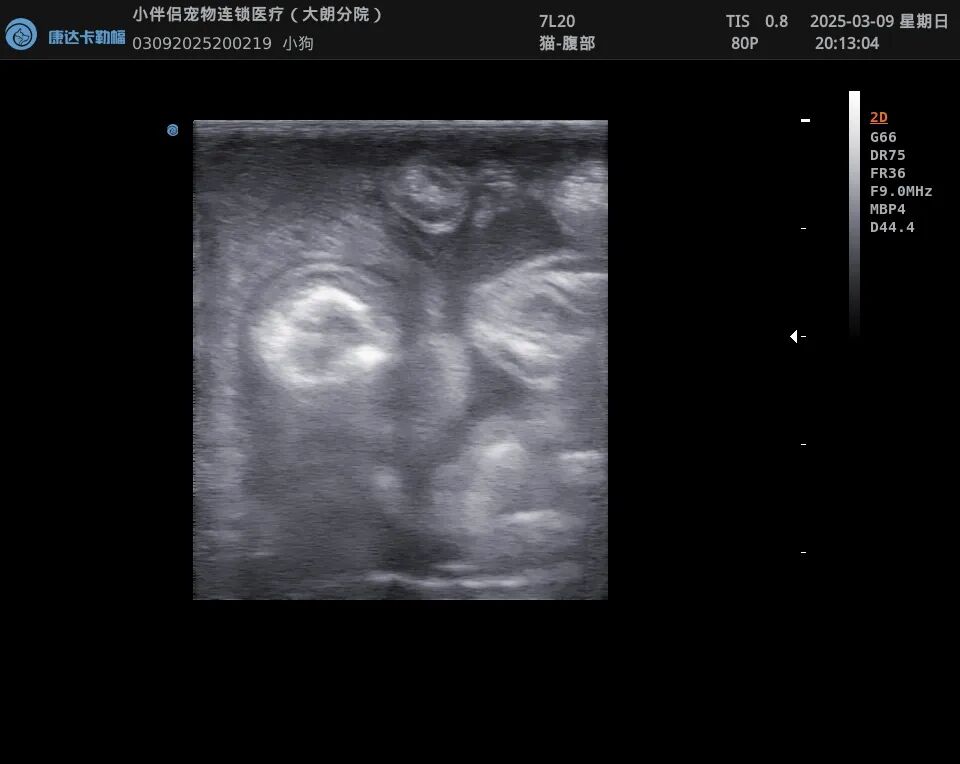

超声可见腹腔内大量游离的液性暗区,肠系膜淋巴结肿大。

图片

腹水穿刺李凡他试验阳性,细胞学以炎性细胞为主。